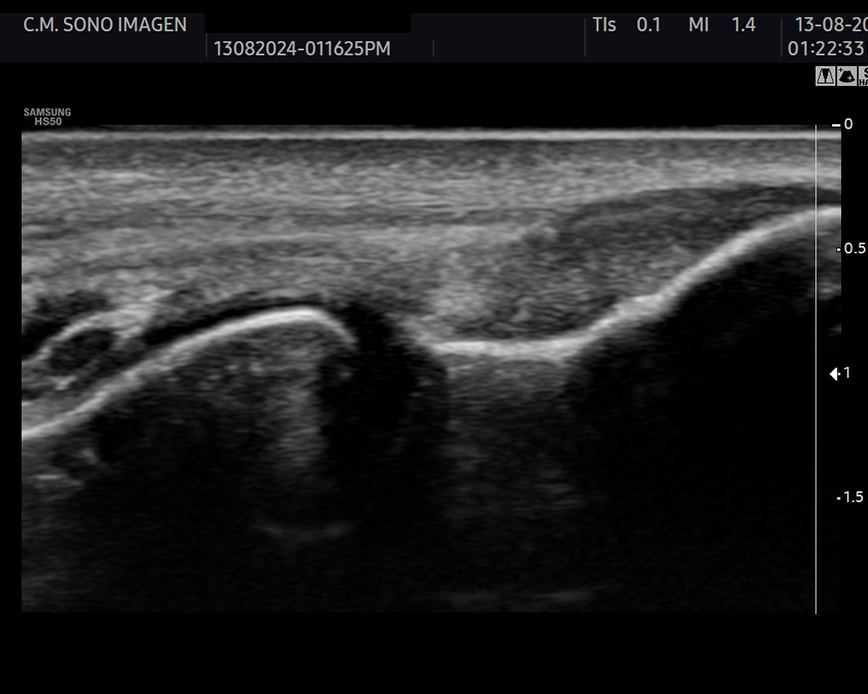

Es un procedimiento no invasivo y seguro , incluido niños, ya que no usamos radiación ionizante. Permite realizar un diagnóstico en tiempo real y podemos evaluar tendones, músculos, ligamentos, articulaciones y nervios.

¿Qué ecografías realizamos?